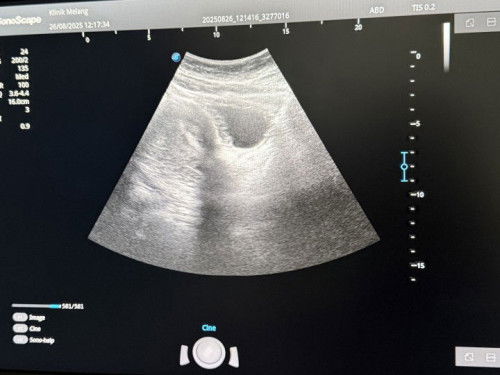

Lmp 13 jun. Dah 2 bulan tak period. Upt duk negatif. Aku buat scan, jumpa kantung. Dr bagi ubat turun darah sebab cakap tak menjadi. So aku patut makan tak ubat tu? Ada tak yang macam aku tapi kandungan menjadi?

dktr mesti dh buat evaluation sblm bg ubat. plus upt pun dh -ve. klu diagnose kantung xmenjadi lebih baik dikeluarkan. klu x masalah lain pula akn dtg spt infection

kadang upt x accurate. cuba buat blood test beta HCG kalau still xde jugak boleh follow doctor.

ni scan dri atas je ke? try pegi klinik lain utk scan dri bawah pulakk